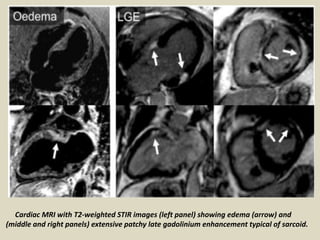

Cardiac MRI with T2-weighted STIR images (left panel) showing edema (arrow) and

(middle and right panels) extensive patchy late gadolinium enhancement typical of sarcoid.